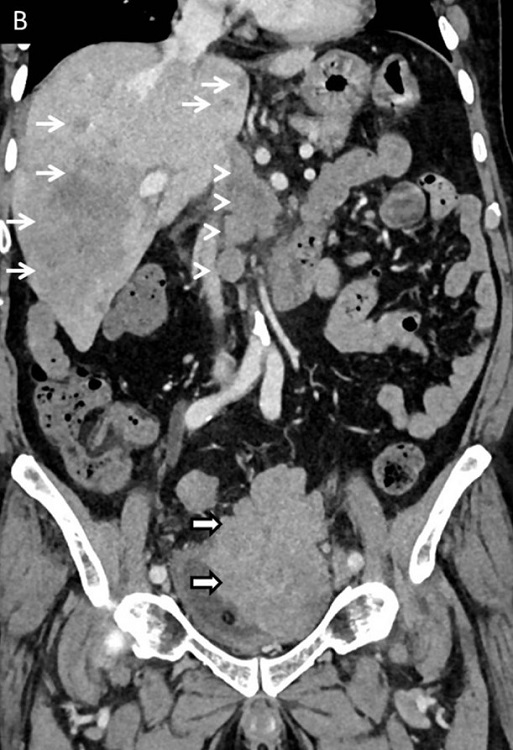

An 81-year-old man was referred to the Urology Department to manage a high-grade, poorly differentiated carcinoma of the urinary bladder, reported on a biopsy performed outside. He had a history of repeated episodes of gross hematuria, weight loss, and reduced appetite. On evaluation, he was found to be cachexic, with pallor and icterus. He was anemic, with raised bilirubin and mildly altered liver enzymes. The contrast-enhanced CT scan showed a lobulated enhancing bladder mass with a paravesical extension (Figure 3), abdominal lymphadenopathy and multiple liver metastases

. The initial biopsy was reported elsewhere as poorly differentiated carcinoma. IHC was not performed on the initial biopsy. The slides were reviewed. Sections from the lesion showed a proliferation of tumor cells arranged in sheets and nests, with moderately pleomorphic small cells, with scant cytoplasm, hyperchromatic round to overlapping oval nuclei, and inconspicuous nucleoli (Figure 4A). Brisk mitoses (>50 mitotic figures/10HPF) and a few karyorrhectic debris were noted. Hemorrhage and necrosis were also seen. On IHC, the tumor cells were positive for neuroendocrine markers, chromogranin (Figure 4B), and synaptophysin. The tumor cells also expressed positivity for EMA and p63. The tumor cells were negative for LCA, ruling out the differential diagnosis of lymphoma (Figure 4C). Based on these findings, a final diagnosis of SmCC was given. Ki-67 labeling index was 99% (Figure 4D). The patient was advised on the prognosis and started on palliative care. He is currently on follow-up (seven months to date).